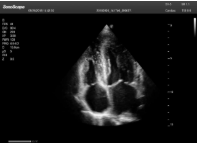

3線陣探頭

探頭面是平面,接觸面大,成像視野呈矩形,成像分辨率高,穿透力相對較低,適用于淺表的血管、小器官、肌骨等檢查。

甲狀腺結(jié)節(jié)